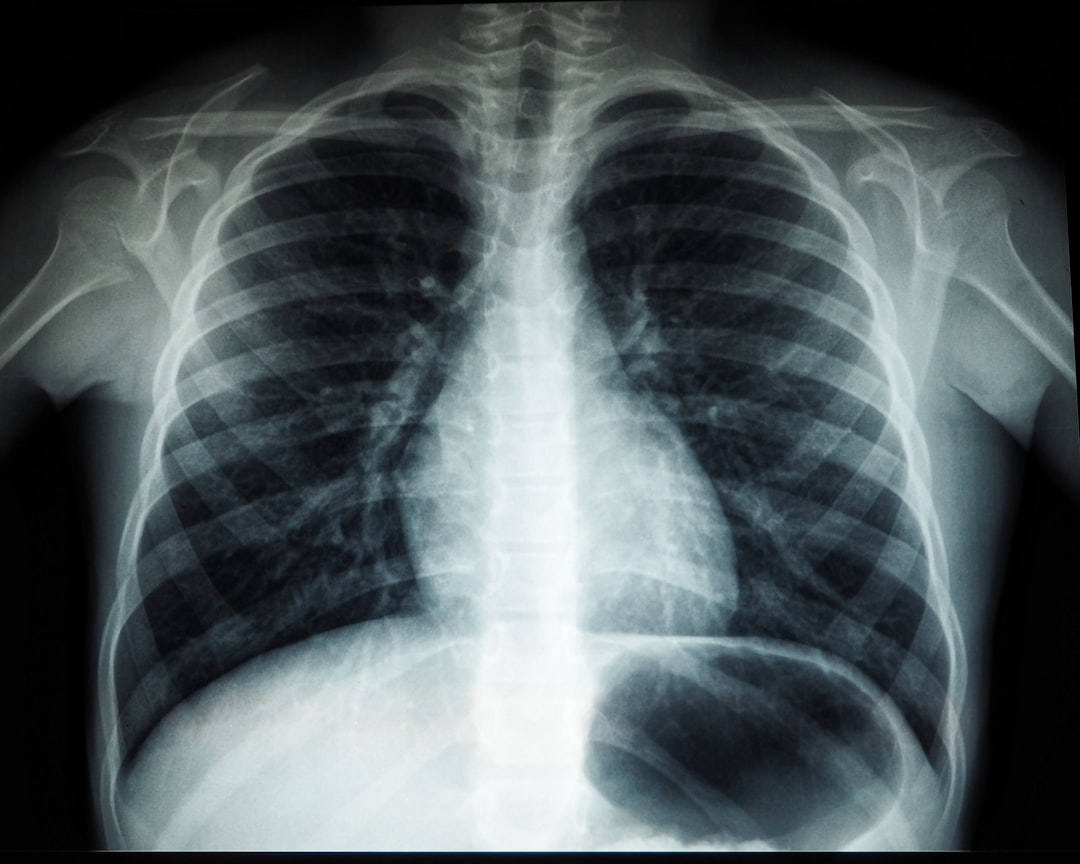

결핵은 폐를 주로 공격하지만, 몸의 다른 부위에도 영향을 줄 수 있습니다. 이 병은 전염성이 강해, 특히 밀접한 환경에서 감염될 가능성이 높습니다. 그래서 보건소에서 제공하는 무료 결핵검사 및 치료 방법은 매우 중요합니다. 검사는 간단하고 빠르며, 일반적으로 X-ray 또는 가래 검사로 이루어집니다. 이런 검사를 통해 조기 발견이 가능해지니, 정기적으로 검사를 받는 것이 좋습니다.